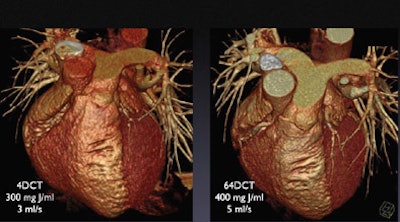

| Greater iodine concentration was a principal cause of improved image quality in two CTA scans of the same patient performed six years apart. Image (right) acquired in 2004 on a 64-slice scanner using 400 mL/kg at 5 cc/sec shows significantly better enhancement in the peripheral regions compared to the first scan (left) performed in 1998 on a four-slice scanner using 300 mL/kg iodine concentration injected at 3 cc per second. All images courtesy of Dr. Christoph Becker. |

"Because of the higher concentration of iodine in the pulmonary arteries, we see much (farther) into the periphery," he said of an image acquired with the higher-concentration Iomerol 400 agent (Bracco, Milan). The concentrated formula is approved for use in Europe, but not in the U.S.